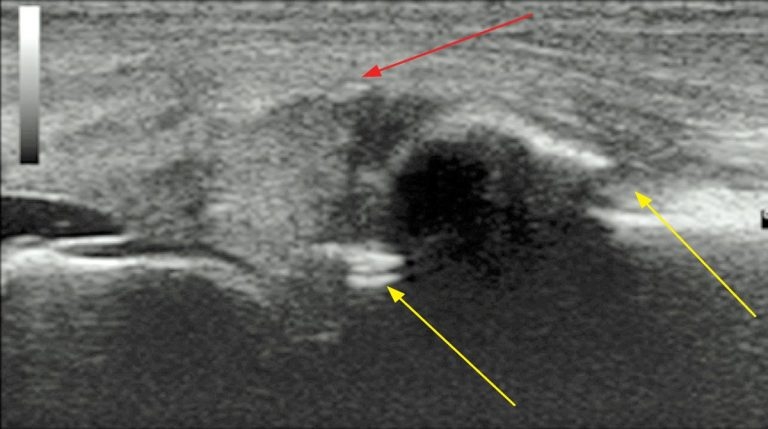

Ultrasound examination is very useful to assess joint disease (Figure 5). It allows visualisation of the periarticular soft tissues, the presence and character of joint effusions – which may be variably palpable – as well as the articular cartilage and bone surfaces. Linear 7.5 megahertz (MHz) to 12MHz ultrasound probes usually provide adequate diagnostic imaging of the majority of equine diarthrodial joints.